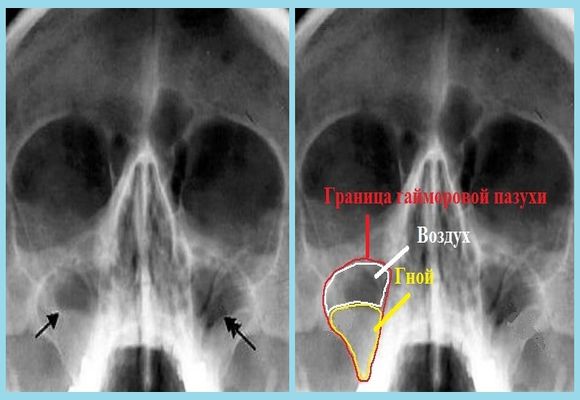

КТ-снимки хронического этмоидита: подробная визуализация